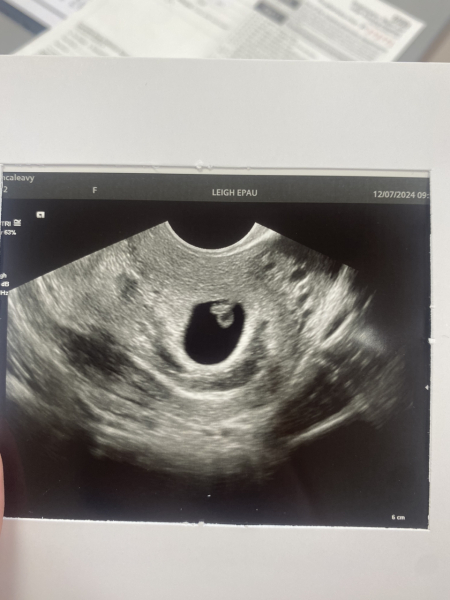

Hi I thought I'd give an update. I had a scan yesterday, the doctor was actually concerned I could have an ectopic pregnancy as well as one in my uterus so that was checked! There is definitely only one baby who is in the right place with a strong heartbeat :) We did find quite a large subchronic hematoma which must be the cause of the pain as well as the bleeding. It's crazy really as anywhere I read said that only mild uterine cramps come with it, which is definitely not the case for me. The SCH is significantly larger than the gestational sack which is a slight cause for concern but as of right now, the doctor didn't seem overly concerned and my baby is healthy so will just be taking it easy.. hopefully this will ease my anxiety for a while 🙈